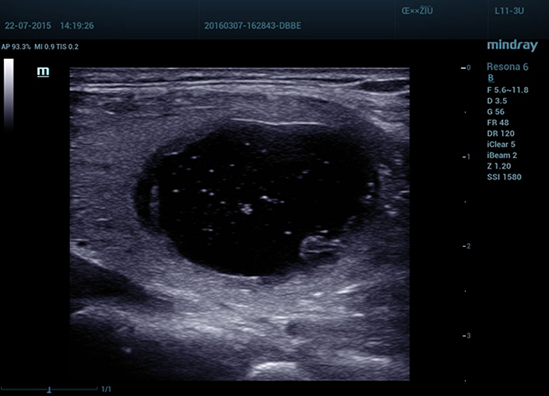

–Ь–µ—В–Њ–і —Н–ї–∞—Б—В–Њ–≥—А–∞—Д–Є–Є Natural Touch

Natural Touch –Њ–±–µ—Б–њ–µ—З–Є—В—М –љ–µ–њ—А–µ–≤–Ј–Њ–є–і–µ–љ–љ—Г—О —З—Г–≤—Б—В–≤–Є—В–µ–ї—М–љ–Њ—Б—В—М –Є –Њ—В–ї–Є—З–љ—Г—О –≤–Њ—Б–њ—А–Њ–Є–Ј–≤–Њ–і–Є–Љ–Њ—Б—В—М —А–µ–Ј—Г–ї—М—В–∞—В–Њ–≤ –≤–љ–µ –Ј–∞–≤–Є—Б–Є–Љ–Њ—Б—В–Є –Њ—В –љ–∞–≤—Л–Ї–Њ–≤ –Њ–њ–µ—А–∞—В–Њ—А–∞, –њ–Њ–≤—Л—И–∞–µ—В –Ї–ї–Є–љ–Є—З–µ—Б–Ї—Г—О –Ј–љ–∞—З–Є–Љ–Њ—Б—В—М –Љ–µ—В–Њ–і–∞ –Є —А–∞—Б—И–Є—А—П–µ—В –≤–Њ–Ј–Љ–Њ–ґ–љ–Њ—Б—В–Є –µ–≥–Њ –њ—А–Є–Љ–µ–љ–µ–љ–Є—П. –£–љ–Є–Ї–∞–ї—М–љ—Л–є –∞–љ–∞–ї–Є–Ј –Ј–Њ–љ—Л –Њ–±–Њ–і–Ї–∞ вАФ –Є—Б–Ї–ї—О—З–Є—В–µ–ї—М–љ–Њ –њ–Њ–ї–µ–Ј–љ—Л–є –Є–љ—Б—В—А—Г–Љ–µ–љ—В –і–ї—П –Њ—Ж–µ–љ–Ї–Є –і–Њ–±—А–Њ–Ї–∞—З–µ—Б—В–≤–µ–љ–љ—Л—Е –Є –Ј–ї–Њ–Ї–∞—З–µ—Б—В–≤–µ–љ–љ—Л—Е –Њ–±—А–∞–Ј–Њ–≤–∞–љ–Є–євАФ –њ—А–µ–і–Њ—Б—В–∞–≤–ї—П–µ—В –і–∞–љ–љ—Л–µ –Њ –Ї–Њ—Н—Д—Д–Є—Ж–Є–µ–љ—В–µ –і–µ—Д–Њ—А–Љ–∞—Ж–Є–Є –Љ–µ–ґ–і—Г –Њ–Ї—А—Г–ґ–∞—О—Й–µ–є —В–Ї–∞–љ—М—О –Є –њ–Њ—А–∞–ґ–µ–љ–љ—Л–Љ —Г—З–∞—Б—В–Ї–Њ–Љ, —З—В–Њ –њ–Њ–Ј–≤–Њ–ї—П–µ—В –Њ—Ж–µ–љ–Є—В—М —Б—В–µ–њ–µ–љ—М –Є–љ—Д–Є–ї—М—В—А–∞—Ж–Є–Є —А–∞–Ї–Њ–≤—Л—Е –Ї–ї–µ—В–Њ–Ї –≤ –Њ–Ї—А—Г–ґ–∞—О—Й–Є–µ –Њ–њ—Г—Е–Њ–ї—М —В–Ї–∞–љ–Є.